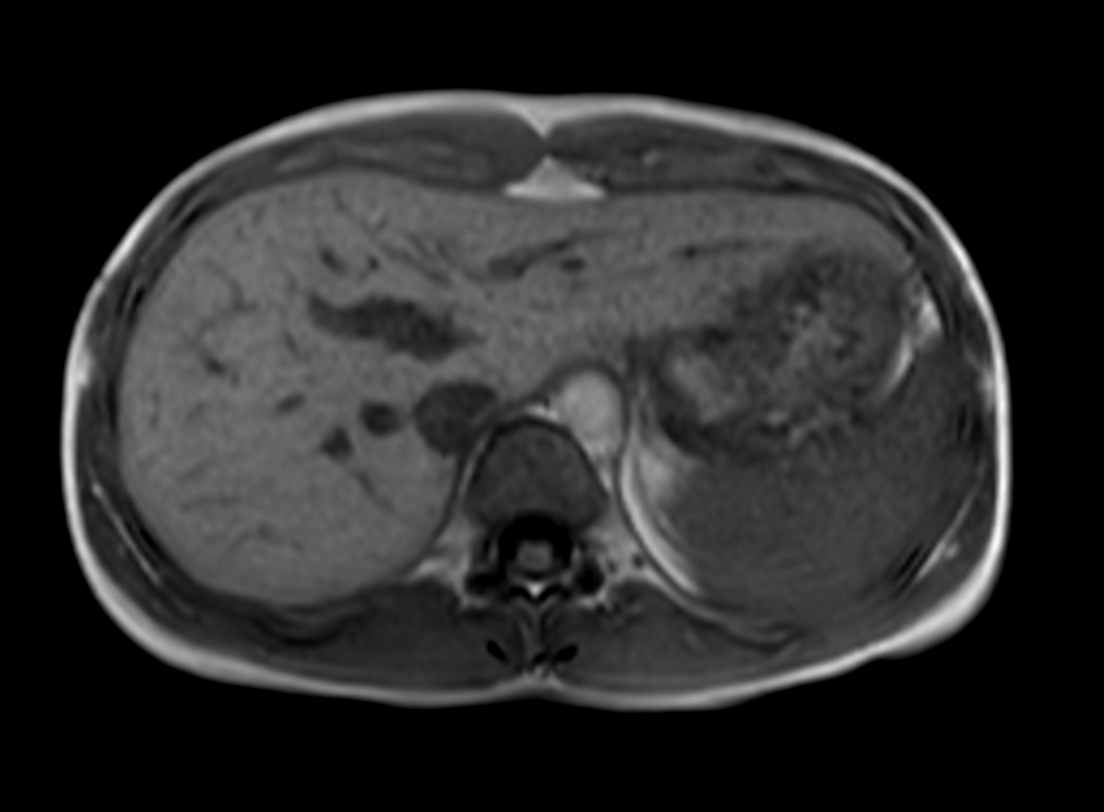

Axial mDIXON XD - T1w FFE (Water only)

Axial mDIXON XD - T1w FFE (In Phase)

Axial mDIXON XD - T1w FFE (Out Phase)